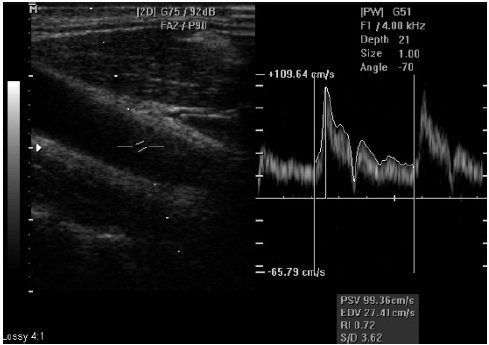

Avalie a imagem abaixo e marque a opção correta.